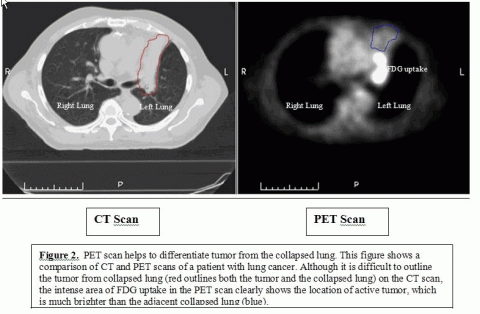

The success of radiation therapy for the treatment of cancer is critically dependent on how accurately and precisely we are able to detect the location and amount of cancer in your body. With current imaging technologies used in radiation therapy planning such as CT scan, and PET scan, we are only able to detect cancer when it is at least 1/3 of an inch in length, or approximately when 1 million cancer cells have formed.